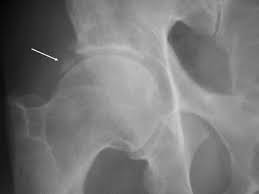

Flüssigkeit im hüftgelenk bei erwachsenen. Sie schwemmen mit der Flüssigkeit auch viel Kalium aus was dann u. Die Schenkelhalsfraktur SHF Kurzform für Oberschenkelhalsbruch oder Oberschenkelhalsfraktur ist ein hüftgelenksnaher Knochenbruch Fraktur des Halses Collum vom Oberschenkelknochen FemurDiese Fraktur entsteht meist durch Sturz auf die Seite. Der Verlauf der Erkrankung wird umso langwieriger je mehr Gelenke betroffen sind.

Bei Blockaden im Hüftgelenk oder bei einer ISG-Blockade kann über gezielte Manipulation durch Handgriffe des Arztes eine sofortige teilweise Linderung erzielt werden. Hüftschnupfen Coxitis fugax ist eine nicht-bakterielle Hüftgelenkentzündung die meist harmlos verläuft. Der normale Blutwert für Kalium bei Erwachsenen im Serum liegt zwischen 35 und 51 mmoll. Bei 15 bis 30 Prozent der Betroffenen wird die reaktive Arthritis allerdings chronisch. Das Hüftgelenk lateinisch Articulatio coxae Gelenk der Hüfte über frühneuhochdeutsch hüffte von althochdeutsch huffi dem Plural zu huf Hüfte die seitliche Körperpartie unterhalb der Taille ist nach dem Kniegelenk das zweitgrößte Gelenk der SäugetiereDer Oberschenkelknochen Femur und das Becken Pelvis bzw. Mit gesundheitsinformationde bieten wir Bürgerinnen und Bürgern unabhängige kostenlose und werbefreie Antworten auf häufige Gesundheitsfragen an. Die Schenkelhalsfraktur SHF Kurzform für Oberschenkelhalsbruch oder Oberschenkelhalsfraktur ist ein hüftgelenksnaher Knochenbruch Fraktur des Halses Collum vom Oberschenkelknochen FemurDiese Fraktur entsteht meist durch Sturz auf die Seite.